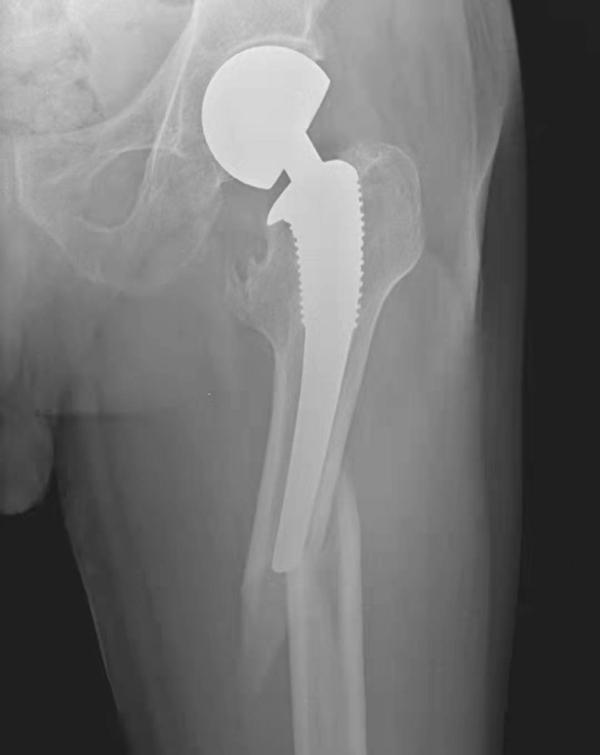

四、异位骨化

全髋关节置换术后,大约有39%以上的患者可发生邻近软组织骨化,术后2~4周的X线片上常能表现出来,而骨化灶成熟要1年以上时间。X线片上表现股骨假体颈部的周围可见斑片状或条片状骨化阴影,大小范围不一(图6~图8)。

图6 右侧人工髋关节置换术后异位骨化

平片,右侧人工髋关节外方可见条片状骨化影